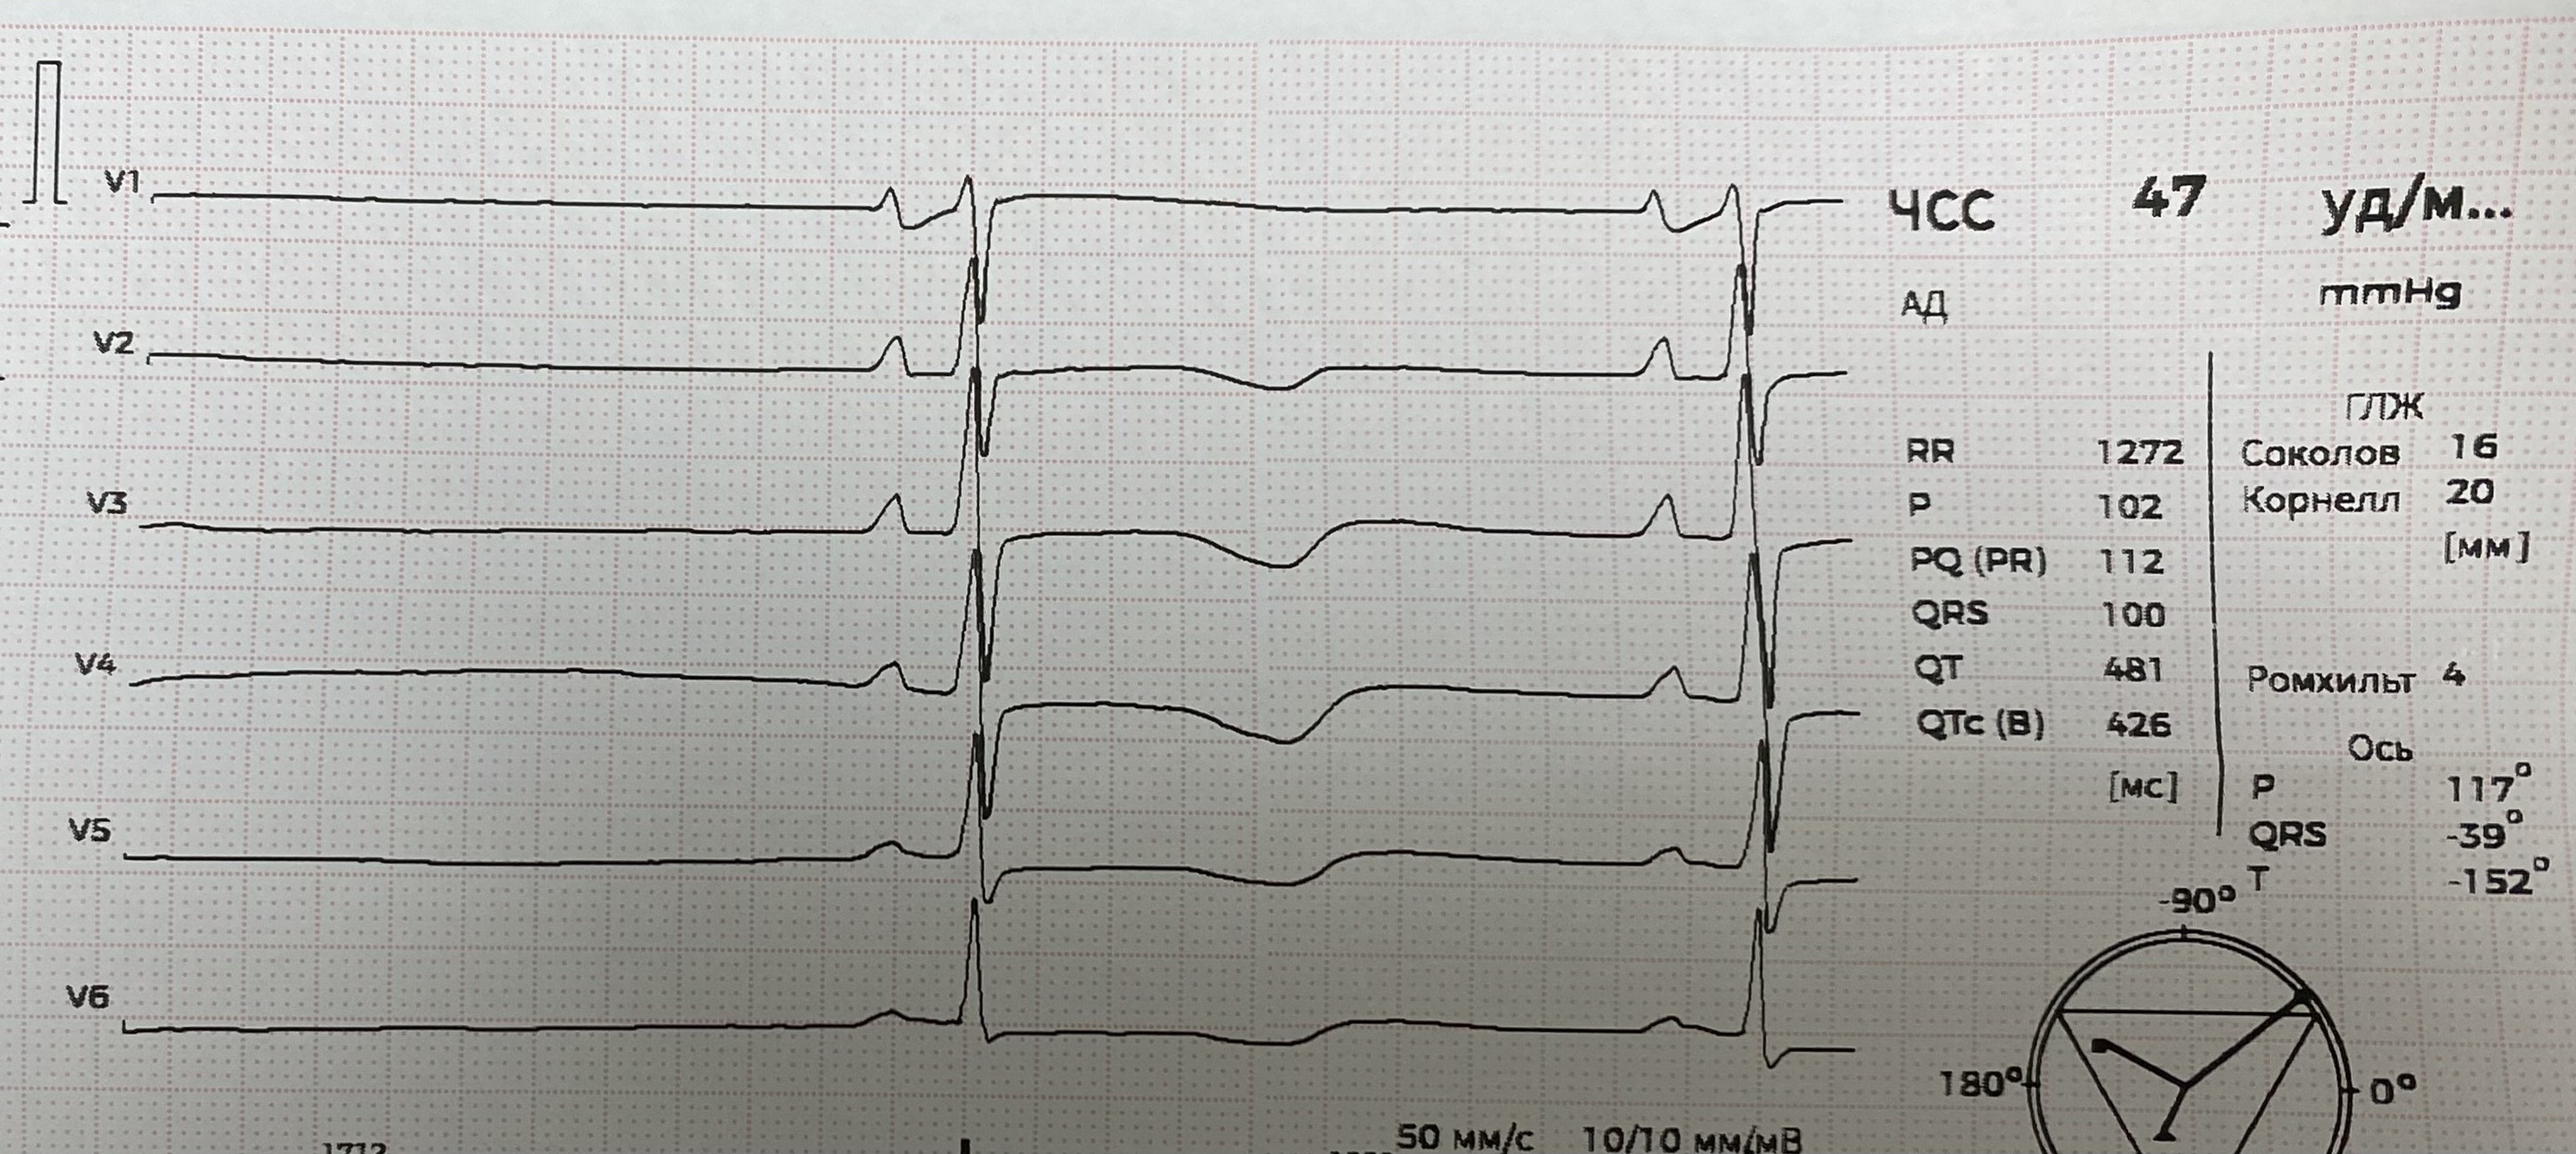

СА блокада